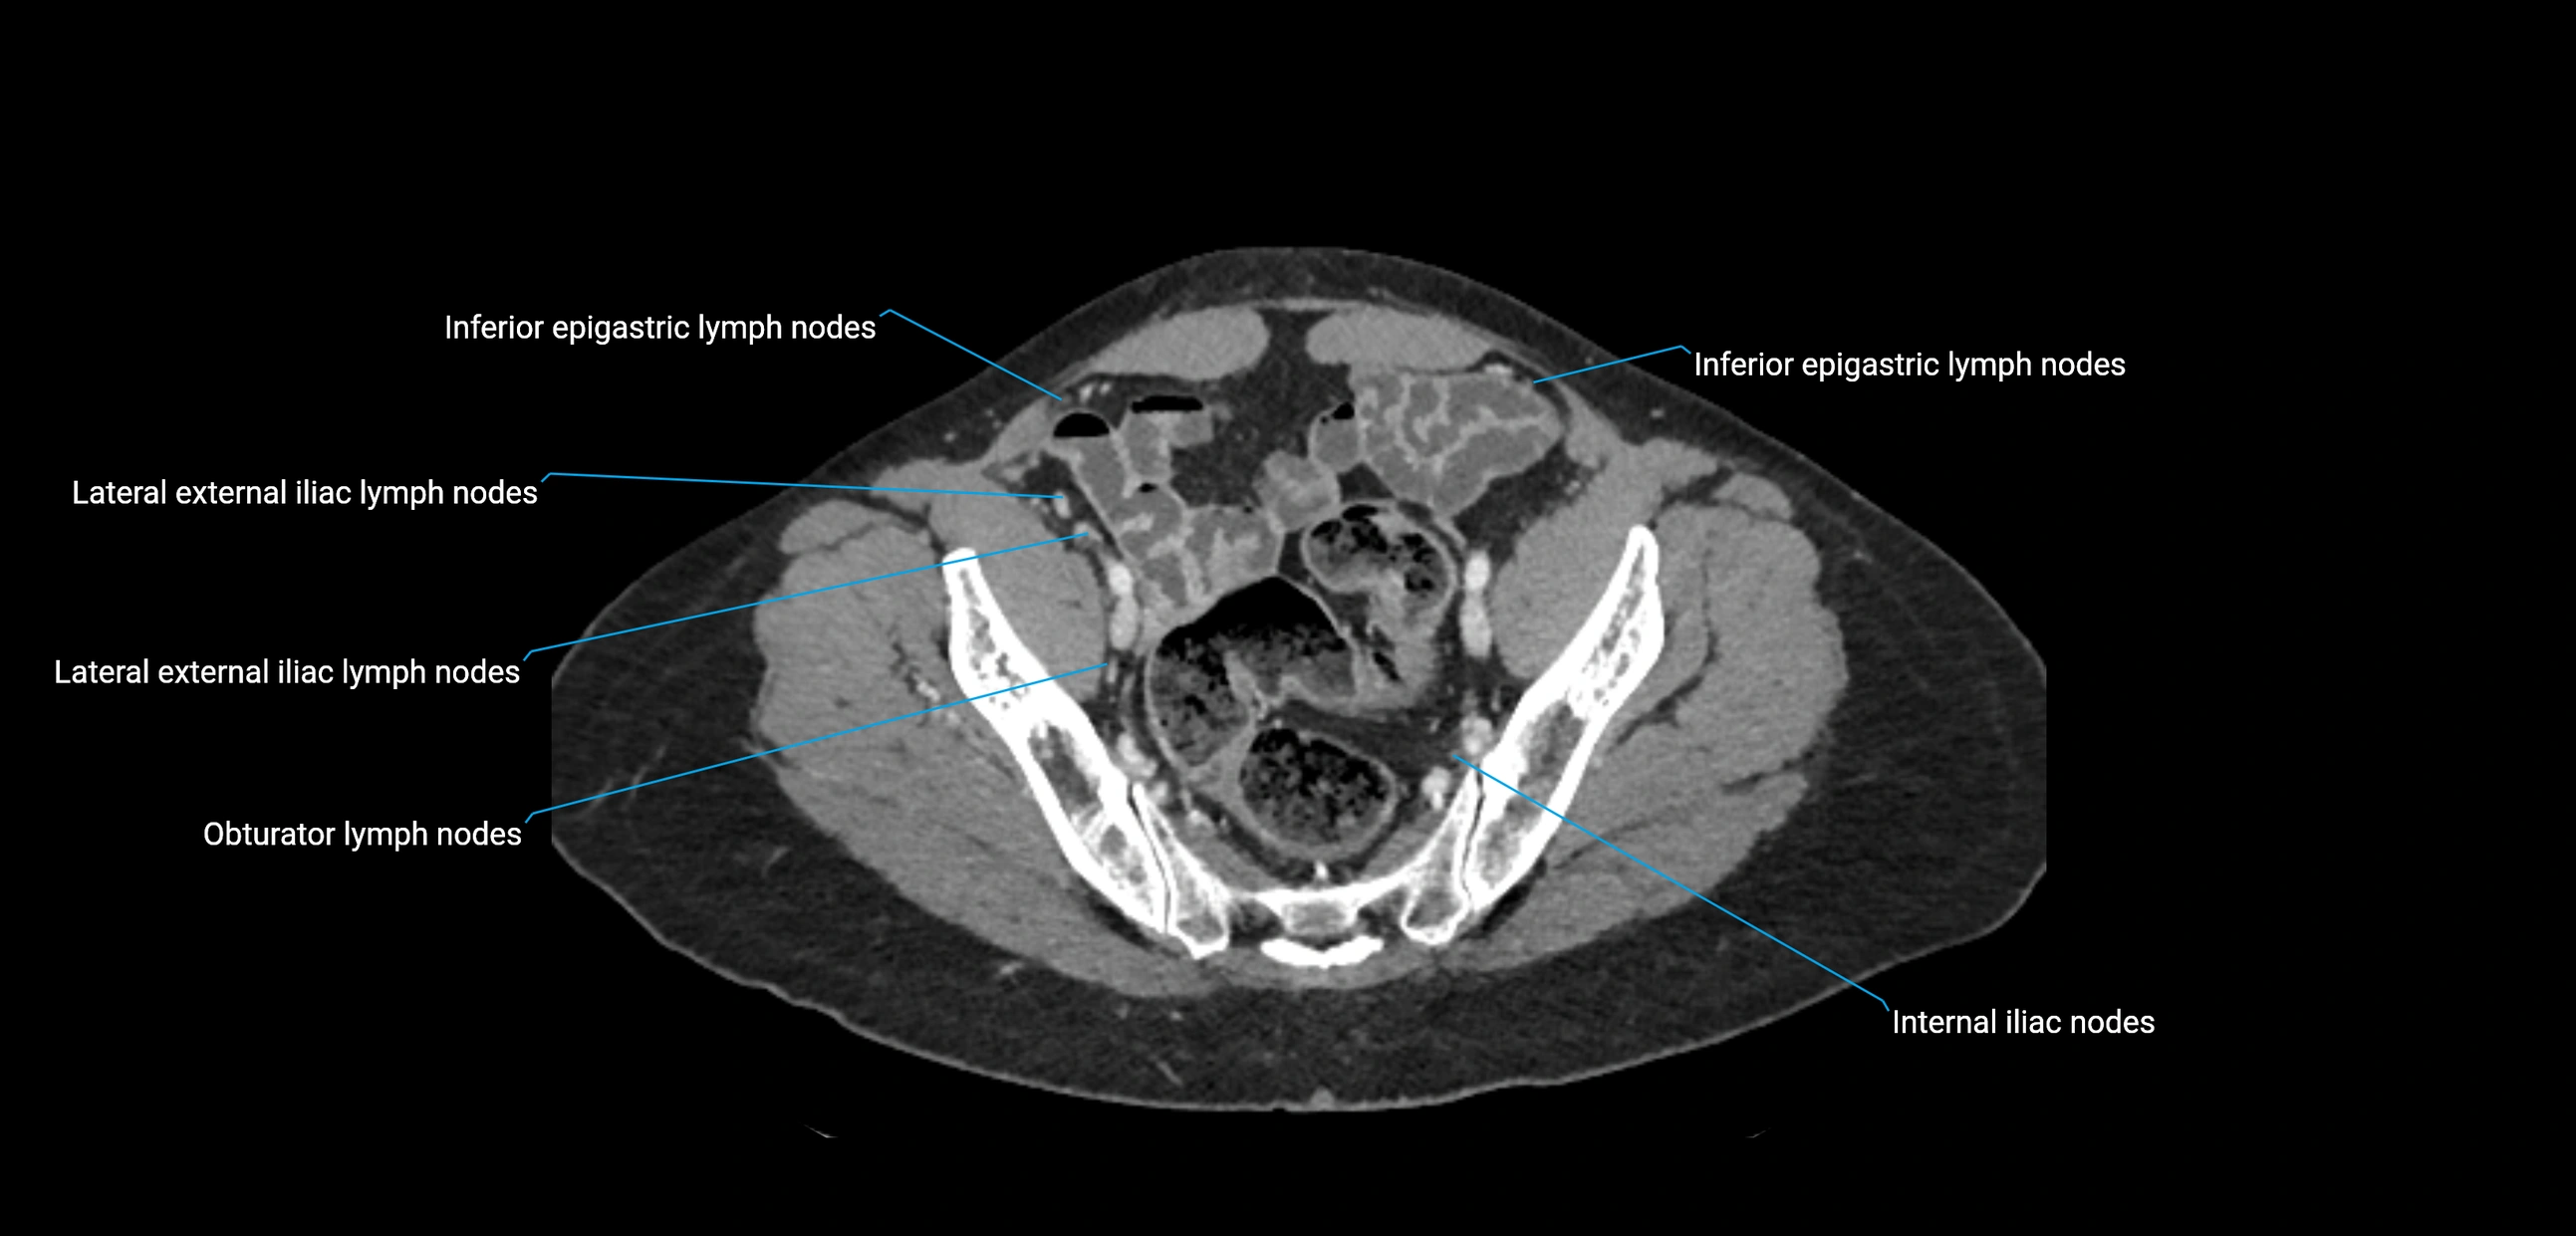

CT image

image